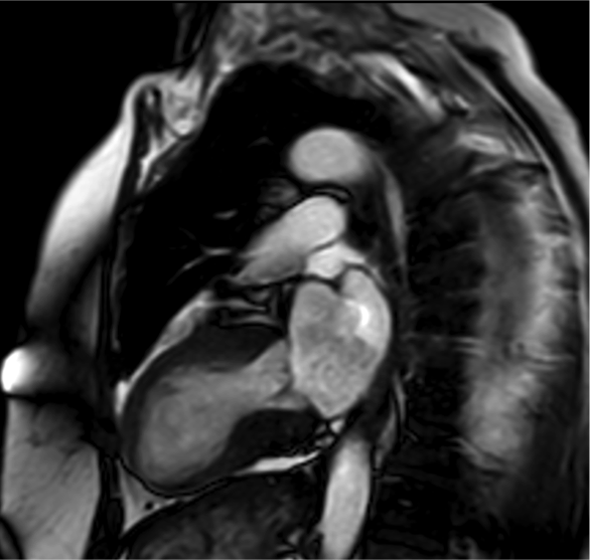

El resultado de la coronariografía fue: arterias coronarias sin lesiones. Depresión moderada-grave de la FEVI por extensa discinesia de los segmentos medio-apicales. Se completa estudio con ecocardiografía y RM cardiaca.

- E. Miocardiopatía de estrés con realce tardío no típico.